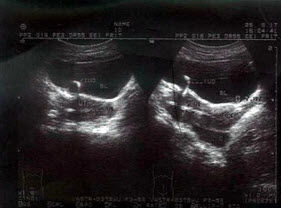

女性,27岁,停经49天,尿妊娠试验阳性。如图所示,超声诊断为()

A.宫腔积液

B.早孕,多胎妊娠

C.绒癌

D.葡萄胎

E.稽留流产